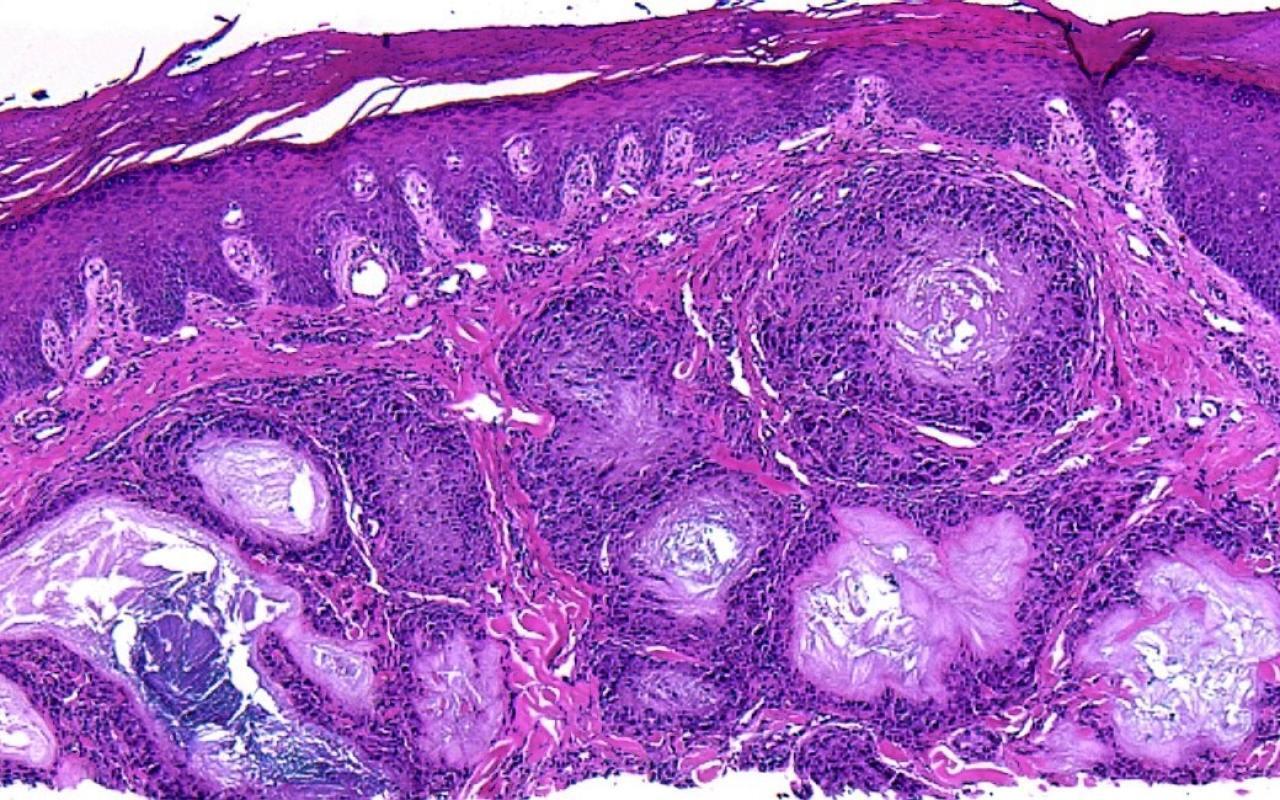

1. Which of the following is the most likely diagnosis of this image?

Correct choice:C. Metastatic adenocarcinoma

Explanation: In this image, the lymphatics are filled with large atypical cells trying to form glands making metastatic adenocarcionma the most likely diagnosis. Merkel cell carcinoma is a sheet of blue cells with salt and pepper nuclei. A lipoma is a collection of normal fat. Melanoma would have nests of atypical melanocytes. A myxoid neurothekeoma would be a loose collection of cells in thekes with a cellular stroma and the cells do not attempt to form glands.